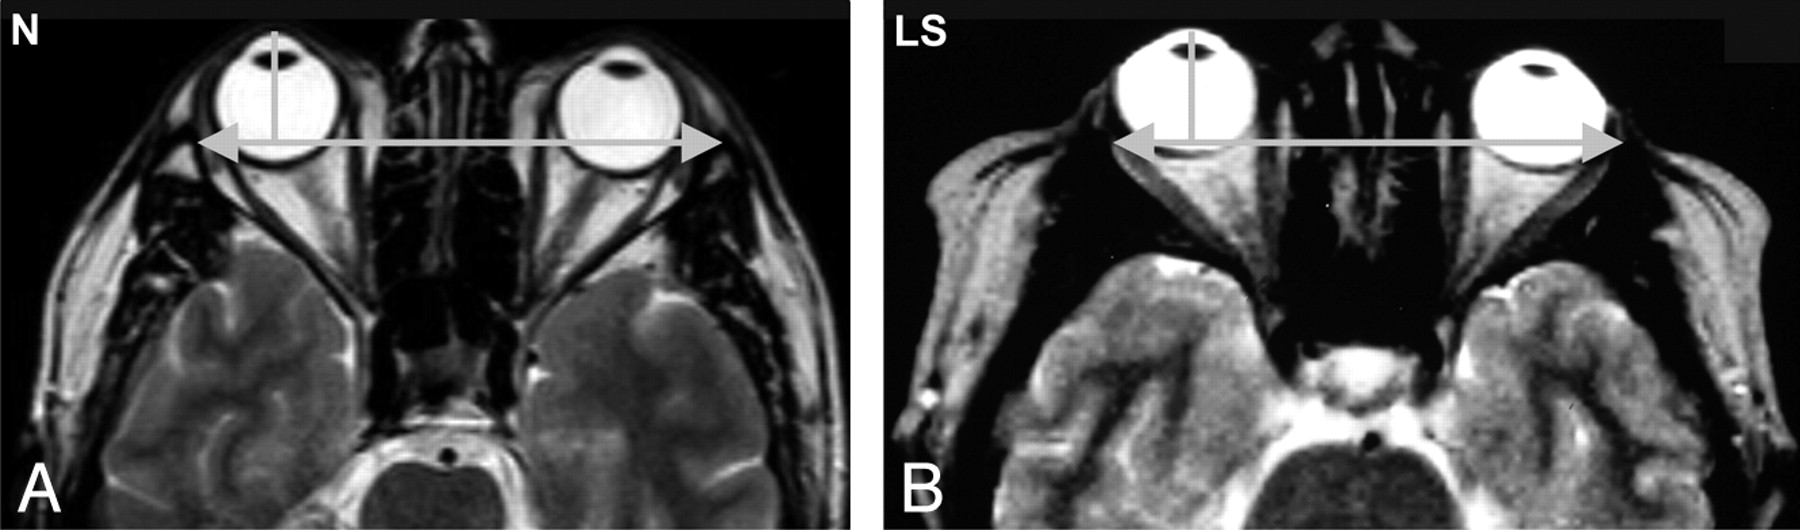

Axial T2-weighted images of the orbits. Note that in LS, the orbits are shallower and the globe is more anterior in relation to the interzygomatic line. N indicates healthy control subject.

The orbital measurements are shown in the Table. Compared with the control subjects, the patients with LS had a significantly smaller maximal globe diameter, shallower but wider orbits due to a shorter lateral wall, a smaller medial distance between the orbits, and a larger angle of the orbit. There was no significant difference in the most anterior diameter of the orbit. Thus, the ratio between the most anterior orbital diameter and the globe was greater in the study group than in the controls. The ratio between the length of the lateral wall of the orbit and the globe diameter was not significantly different in the LS group, and the position of the globe was more anterior in relation to the interzygomatic line but not in relation to the anterior orbital rim (Fig 2).

The present study focused on evaluation of the orbits in LS by MR imaging and adds new data on their shape and size. We found that the bony orbits in the study group were smaller and shallower but wider than those in the control subjects without LS (Table). The lateral wall length was smaller, and the angle of the orbit was larger. There was a lesser medial distance between the orbits than that in controls, with no significant difference in the most anterior orbital diameter (Fig 2).